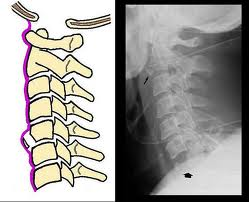

1. La columna cervical es el único segmento vertebral que se afecta en la artritis reumatoide.La evidencia radiográfica de subluxación atloaxoidea anterior , provocada por la rotura o laxitud del ligamento transverso del atlas